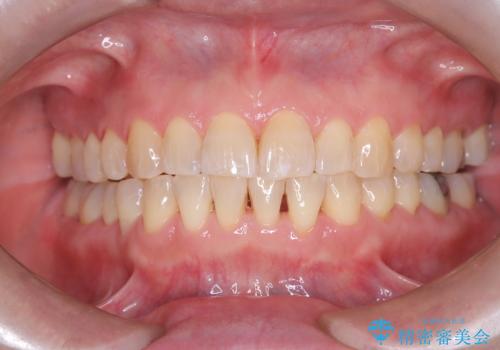

前歯の軽度なガタつきを、1年で美しく整える審美ワイヤー矯正

ワイヤー矯正ならではの確実な歯のコントロールにより、当初の計画通り約1年という短い期間で、前歯のガタつきが解消。見た目が美しく整っただけでなく、清掃しやすい機能的な歯並びを獲得していただけました。